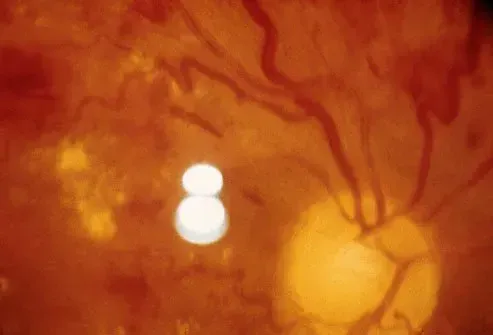

Nogle sygdomme, som du ikke nødvendigvis ville forbinde med øjnene, kan have negativ indflydelse på synet. Diabetes og højt blodtryk kan føre til øjenforhold og synshandicap. Diabetes er en top potentiel årsag til blindhed hos voksne. Diabetisk retinopati er en tilstand, der fører til skade på blodkar, der er placeret i nethinden. Symptomer på diabetisk retinopati kan omfatte uklarhedsproblemer med at opfatte farver mørke områder af syn og flydere. Diabetes kan forårsage besættelse af nethindearterie. Denne tilstand forårsager en blokering i en lille arterie, der leverer blod til nethinden. Højt blodtryk kan potentielt forårsage permanent synstab ved at beskadige nerver og blodkar i øjnene.

Der er to typer aldersrelateret makuladegeneration. 'Våd' AMD er den type, der er forårsaget af blodkar, der lækker blod eller væske ind i makulaen. Tilstanden kan behandles med medicin. 'Dry' AMD er en langsommere sygdomsproces. I denne form vises små gule aflejringer kaldet drusen under makulaen. Der er ingen specifik behandling af tør AMD. Din øjenlæge kan anbefale visse vitamin- og mineraltilskud for at bremse eller stoppe sygdomsprocessen. Lægen kan ordinere et program for synsrehabilitering for at hjælpe dig med at tilpasse dig at leve med AMD.